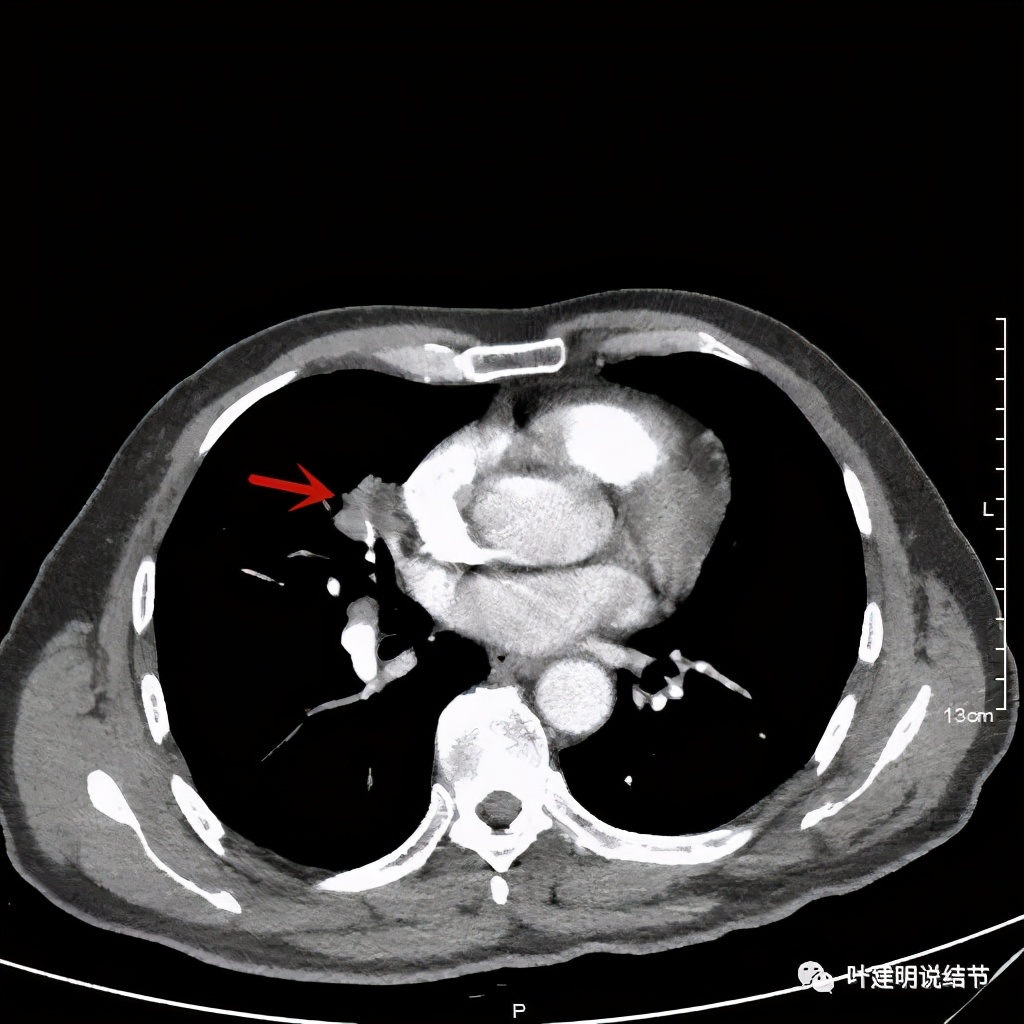

上图示血管被病灶影响,似乎有侵犯

上图示血管在病灶内挤压变细

上图示血管在病灶内被挤压